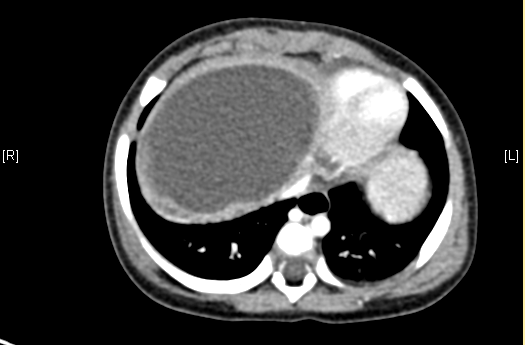

上腹部增强CT:肝右叶囊实性占位。上腹部增强CT示间叶性错构瘤。

术前CT检查:

平衡期